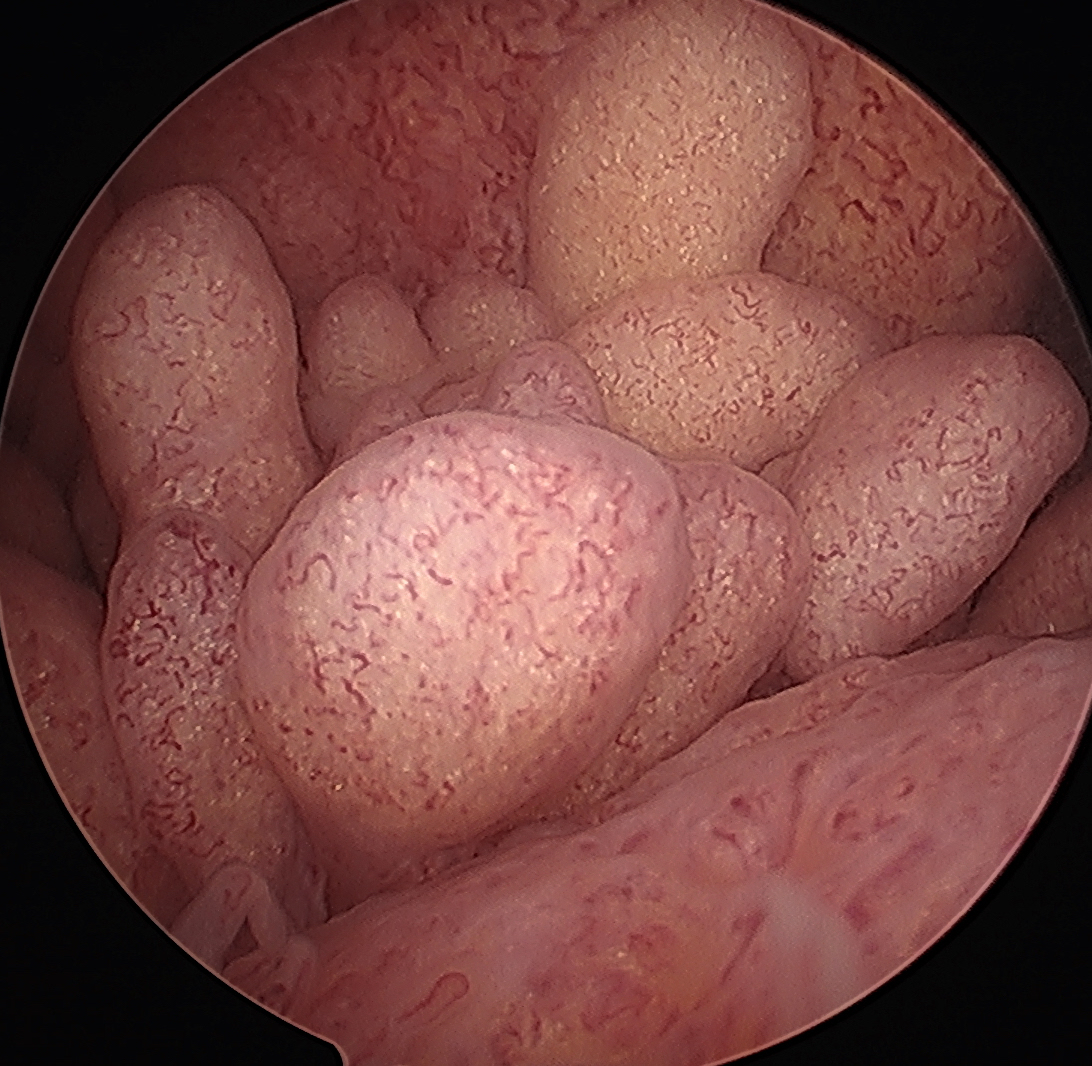

Arthroscopy

Yellow brown polypoid / frond like villous synovitis